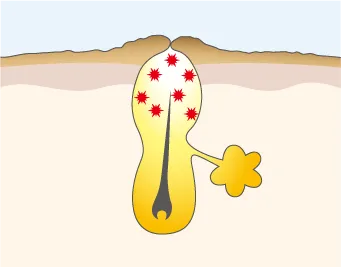

炎症が悪化し膿が溜まる

赤ニキビが進み、膿んでいる状態。ニキビ全体が赤く、毛穴内に膿が溜まり、表面が黄色く見える。